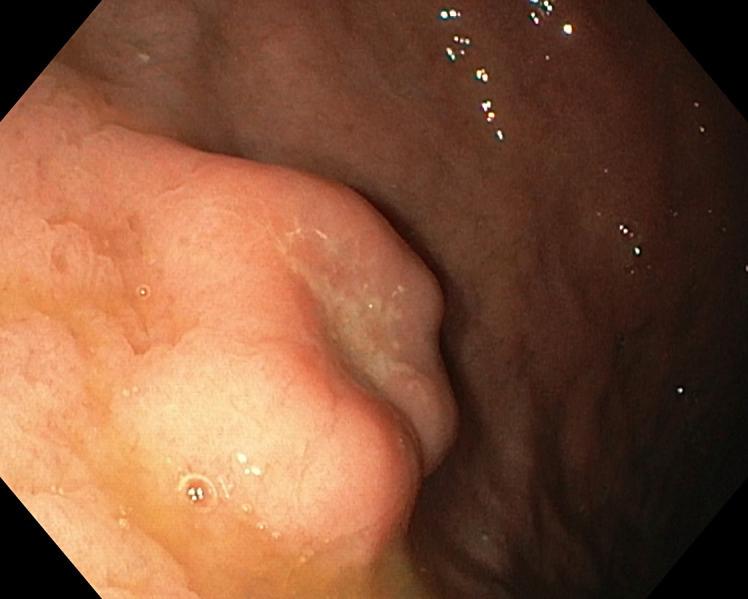

Gastritis Cystica Profunda Presenting as an Ulcerated Subepithelial Lesion.

https://cdn.ncbi.nlm.nih.gov/pmc/blobs/9125/10836860/ce6c9fa2913e/pjg-2024-0031-0001-530669_F01.jpg